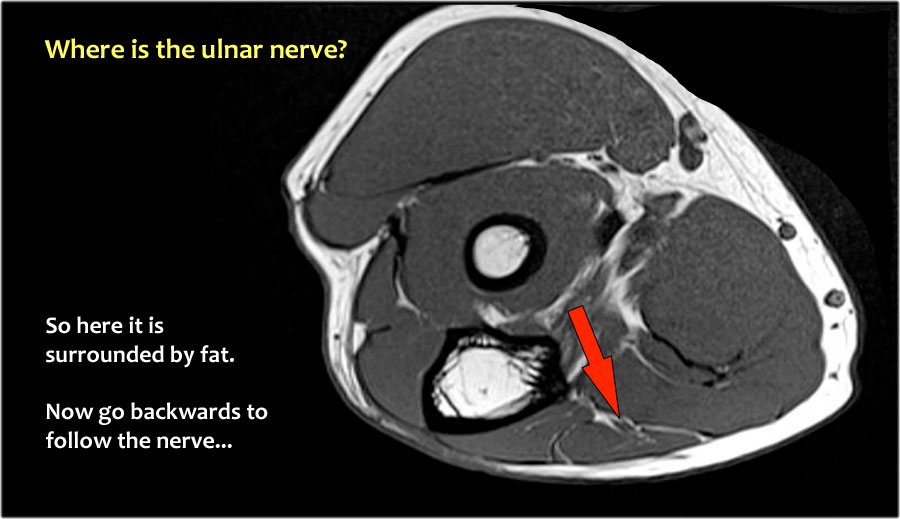

Một cách để thực hiện là đi theo các cấu trúc về phía xa cho đến khi tìm thấy dây thần kinh trụ ở phía xa tại vị trí bình thường của nó ở vùng cẳng tay gần được bao quanh bởi mô mỡ.

Sau đó khi bạn theo dõi nó về phía gần, bạn sẽ nhận thấy rằng đây là một trường hợp chuyển vị dưới da.